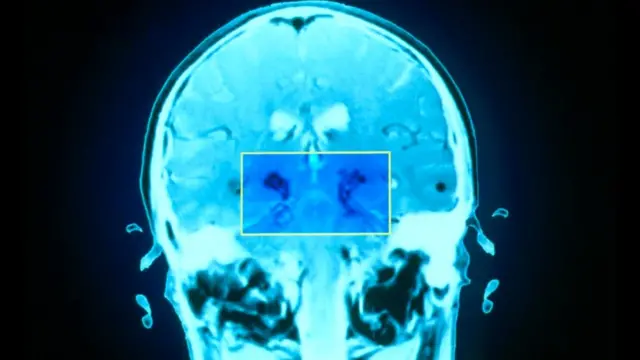

Как ни странно, степень усталости не всегда зависит от масштаба повреждения мозга, однако деятельность некоторых областей мозга все же имеет решающее значение.

К ним относятся области, связывающие лобную кору - испещренную бороздками и напоминающую древесную кору поверхность мозга, расположенную непосредственно за глазницами и отвечающую за сознательное аналитическое мышление, внимание и память - с более глубокими областями мозга.

Последние включают базальные ядра и миндалевидное тело - области, связанные с автоматическими, инстинктивными действиями и поведением.

"Возможно, при нарушении определенных связей мозг уже не так эффективно передает информацию и быстрее устает", - говорит Малли.

Если это так, то для любого вида умственной деятельности потребуется больше энергии. Следовательно, ресурсы организма могут закончиться даже при небольшой нагрузке.